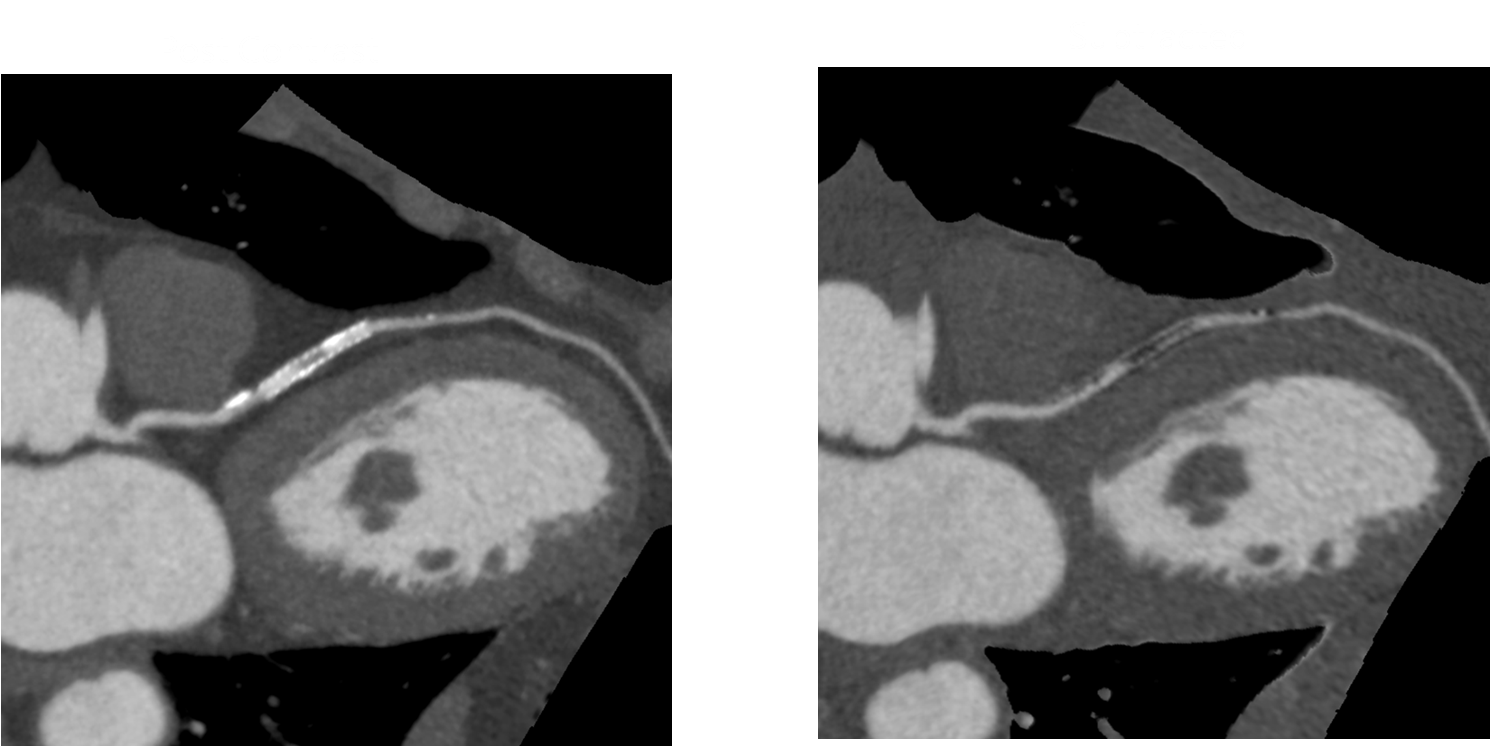

病例四 PCI后復(fù)查,前降支支架內(nèi)再狹窄。

冠脈減影前 冠脈減影后

病例五 高鈣化積分冠脈檢查

心血管方面 佳能640層鐠黃金CT依托0.275秒的掃描速度、16厘米的全器官覆蓋,旋轉(zhuǎn)1圈即可實(shí)現(xiàn)心臟成像,徹底解決了心律不齊、房顫等檢查禁忌,從而根除了錯(cuò)層偽影。同時(shí)掃描劑量大大降低,僅僅相當(dāng)于64排CT的二十分之一,自然本底輻射的八分之一。對(duì)于患有肺心病或患心臟病同時(shí)伴有呼吸系統(tǒng)疾病的病人,即使在不屏氣的情況下,也能獲得高質(zhì)量的心臟圖像。此外還可以對(duì)狹窄斑塊成分進(jìn)行分析,有效預(yù)防急性心肌梗死的發(fā)生,大大降低隱匿性冠心病的致死風(fēng)險(xiǎn)。獨(dú)有的智能冠脈減影技術(shù),可實(shí)現(xiàn)高鈣化積分病人心臟成像和PCI手術(shù)后支架病人的復(fù)查,拓展了冠脈CTA檢查的臨床領(lǐng)域。